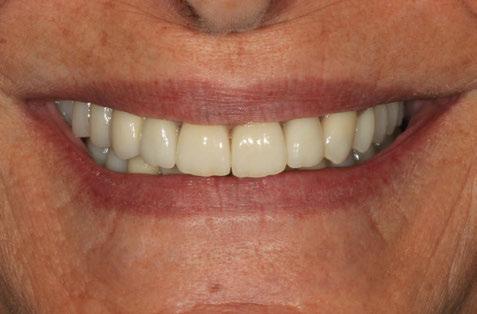

Figuras 4 y 5. Imagen intraoral y de sonrisa de la paciente en la primera visita. En ellas observamos el colapso de la mordida a nivel anterior, con una sobremordida del 100%.

Figuras 18-21. Imágenes iniciales y finales de la paciente a los dos años de seguimiento donde observamos el cambio de la sonrisa y la recuperación de la dimensión vertical realizada con la rehabilitación sobre implantes y la confección de nuevas prótesis sobre implantes en el primer cuadrante y facetas en los sectores anteriores superiores e inferiores.